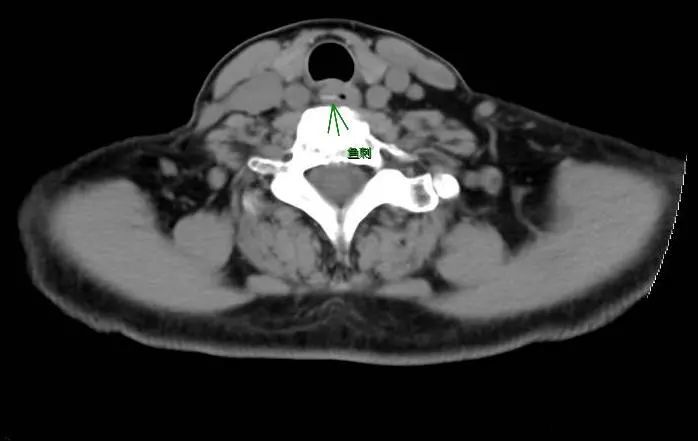

经食道ct检查发现,张先生的食管上段,有一个异物,两端尖锐,很有可能

鱼刺刺入食道焦虑万分,手术联合胃镜化险为夷